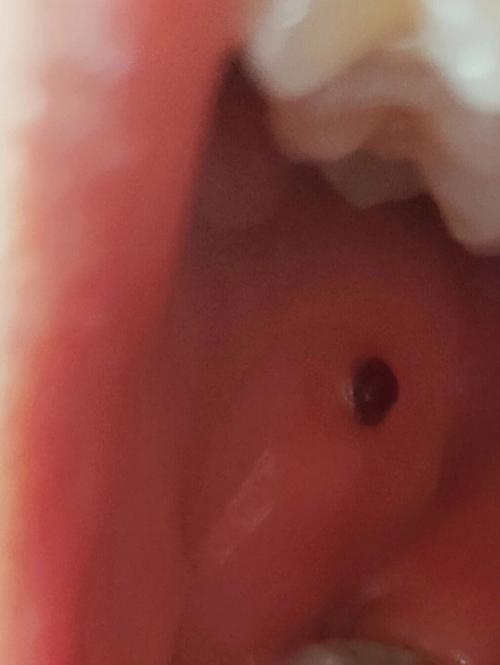

口腔壁上长个血红疙瘩

“血红疙瘩”这个描述很形象,通常意味着这个疙瘩颜色鲜红或暗红,可能与血管有关,或者是其他病变伴有出血倾向。

a. 创伤性血疱或溃疡

- 成因: 这是最常见的原因,可能是你不小心咬到了口腔内壁、吃硬物(如薯片、坚果壳)划伤、或者佩戴的假牙/牙套摩擦刺激导致的,小血管破裂后,血液聚集在黏膜下,就形成了鲜红或暗红色的“血疱”。

- 血疱: 如果表面是完整的、鼓起的,里面充满了液体(血液)。

- 血管痣: 由毛细血管扩张增生形成,通常是扁平或略微凸起的鲜红色或紫红色小点或斑块,按压后可能褪色。

- 化脓性肉芽肿: 也叫“毛细血管瘤”,是一种反应性增生,通常由轻微创伤(如咬伤)引起,它像一个鲜红色或暗红色的“小肉芽”,质地较软,容易出血。

- 特点: 颜色非常“血红”,像一小块血聚集在那里,有些可能会长得比较快。